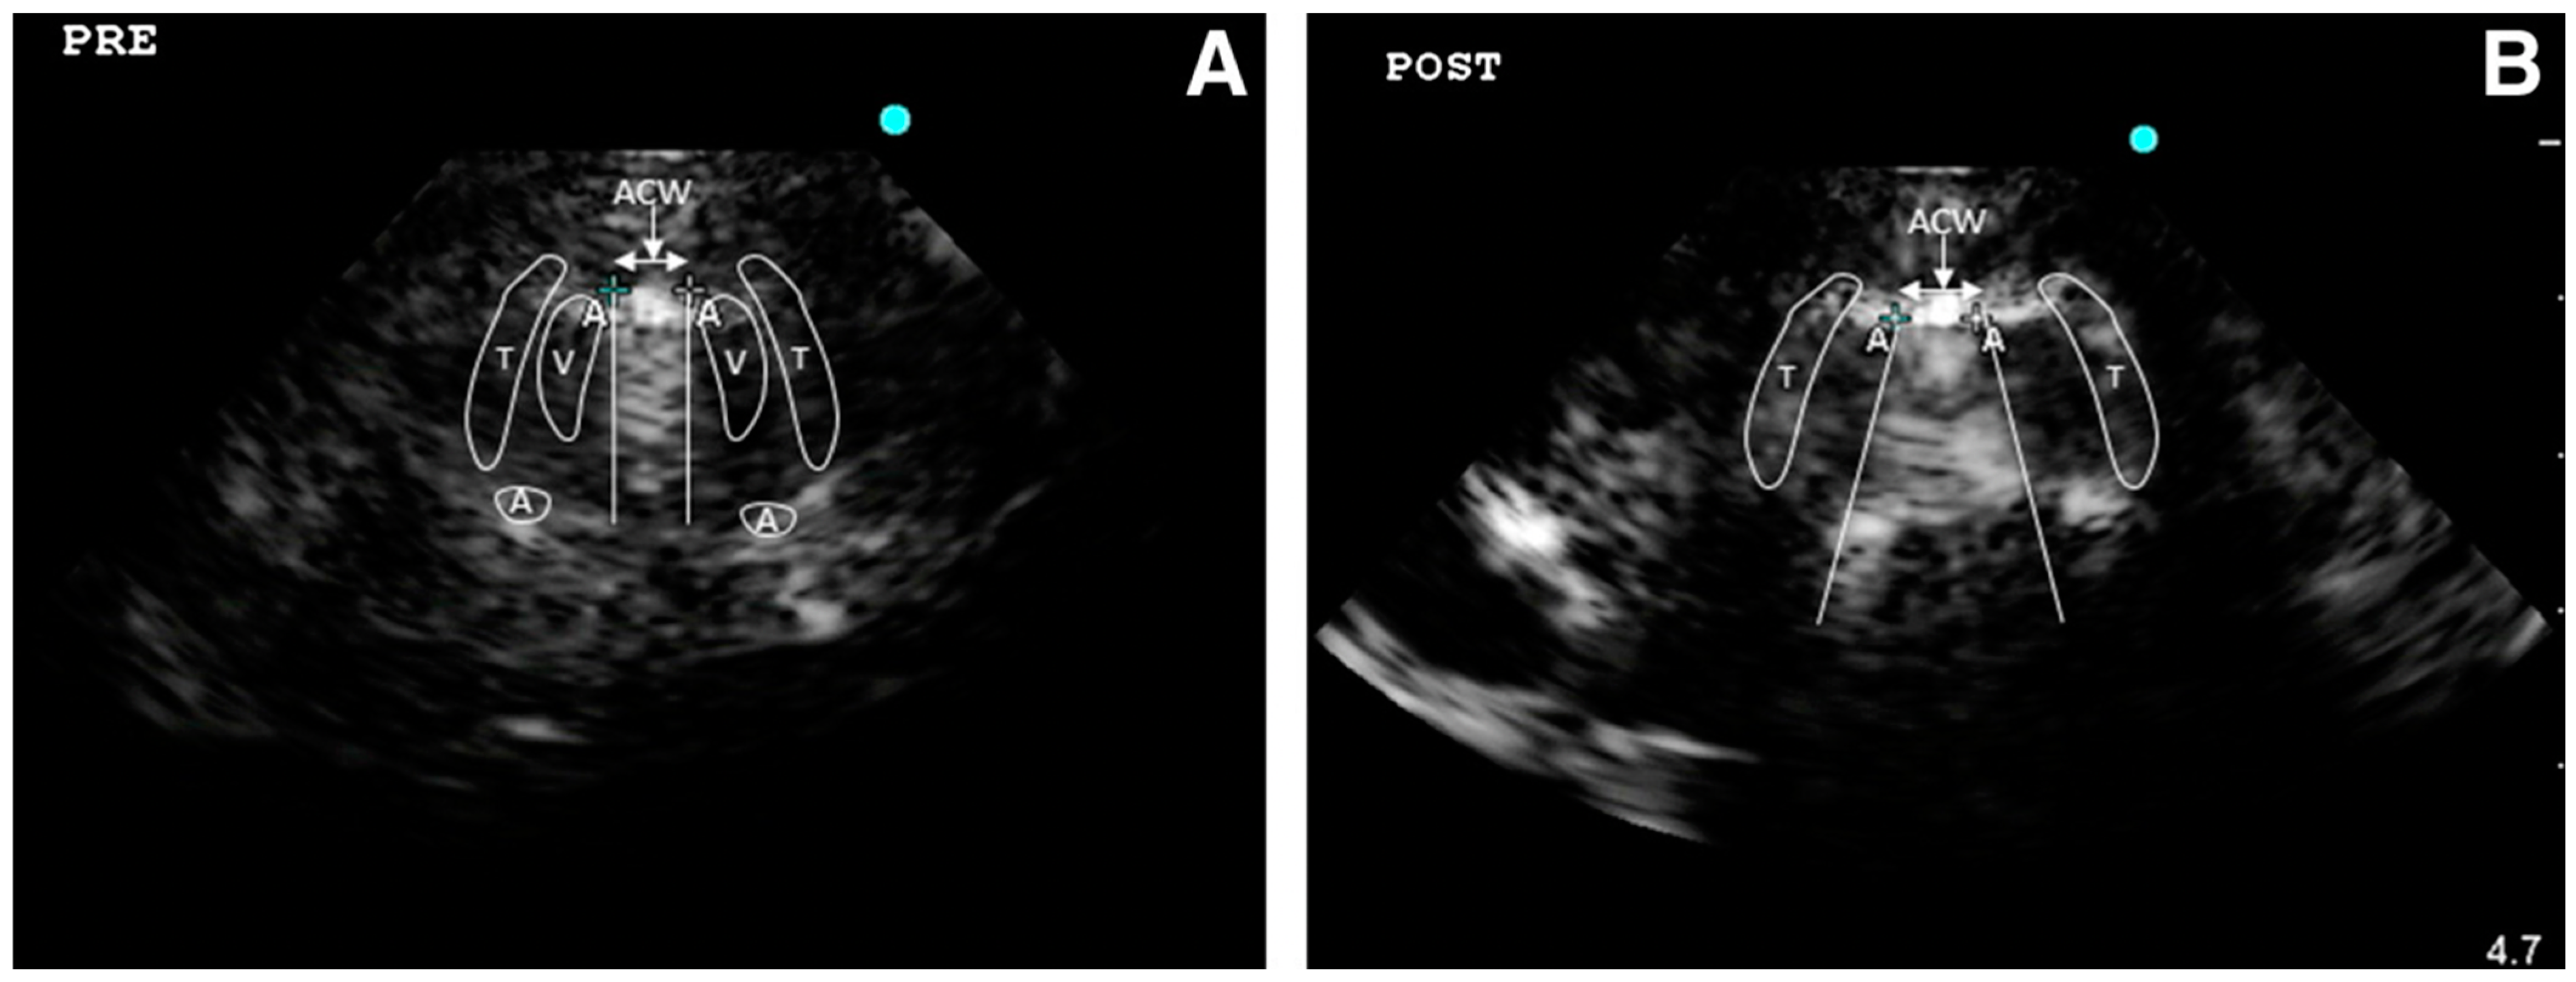

4.1.3. Laryngeal Edema Assessment Pre-Extubation

The assessment of the larynx is important to predict extubation failure. Usually, this is evaluated by a leak test (difference between expiratory tidal volumes with the cuff inflated and deflated). Two prospective observational studies evaluated the air column width differences (ACWD) (width of air between the vocal cords seen by laryngeal ultrasonography) as a predictive index of extubation failure. In the first study ACWD ≥ 1.6 mm predicted laryngeal edema with 0.706 and 0.702 sensitivity and specificity, respectively; the area under the receiver operating characteristic curve of laryngeal ultrasound was 0.823 (95% confidence interval, 0.698–0.947) and that of cuff leak test was 0.840 [19]. In the other study, both laryngeal US and leak test resulted in having a positive predictive value < 20% cuff leak test (cut-off point: 249 mL) and showed a sensitivity and specificity of 75% and 59%, respectively. In addition, laryngeal ultrasonography (cut-off point for air column width: 10.95 mm) resulted in a sensitivity and specificity of 50% and 54%, respectively [17].

A meta-analysis aimed to assess the diagnostic accuracy of ACWD to predict post-extubation stridor analyzed observational studies finding, for a cut-off value from 0.45 to 1.6 mm, a pooled sensitivity and specificity of 0.8 (95% CI = 0.69–0.88, I2: 37.26%, eight studies) and 0.81 (95% CI = 0.72–0.88, I2: 89.51%, eight studies), respectively, and a pooled AUC of 0.87 (95% CI = 0.84–0.90). However, they concluded that the strength of the evidence was poor [22]. From these non-univocal results highlighted by the variability of the reported cut-off, we may argue that the ACWD is a challenging measurement to obtain influenced by operator experience, method standardization and the confounding presence of many artifacts. Further prospective studies are needed to assess its real potential in clinical practice.

Even if the literature on airway US application is still relatively limited, its utilization in clinical practice, both in pre-hospital and emergency hospital settings, is increasing and US can be considered a useful tool to support physicians in airway management especially when they are difficult (Figure 3).

Figure 3.

The imaging from laryngeal ultrasound demonstrates the air column width before (A) and after (B) endotracheal tube cuff deflation. After cuff deflation, the fan-shaped widening air column width obliterates surrounding structures such as vocal cords and arytenoid cartilage by acoustic shadow (T, thyroid cartilage; V, vocal cord; A, arytenoid cartilage). Reproduced with permission of Dr. Sutherasan from [16].